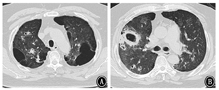

患者男,64岁,因"反复咳嗽、咳痰、喘憋18年,加重20余天"于2018年1月26日入院。患者近18年反复出现咳嗽、咳痰、喘憋,诊断为COPD、肺气肿、肺大疱、矽肺Ⅰ期等。近3年因COPD急性加重多次住院,经抗感染、化痰、平喘等治疗可好转,院外长期吸入沙美特罗替卡松粉(舒利迭)、噻托溴铵粉(思力华),口服止咳、化痰药物。2018年1月3日患者受凉后再次出现咳嗽、咳痰、喘憋加重,就诊于北京某医院。2018年1月3日胸部CT示两肺见多发粗大索条影,边缘模糊,肺气肿,多发肺大疱,左肺下叶球形肺不张,双侧胸膜肥厚,右侧胸膜钙化,右肺下叶支气管扩张(图1),考虑肺部感染。住院后给予哌拉西林舒巴坦钠、比阿培南、莫西沙星等抗感染,并给予甲泼尼龙抗炎(具体不详)。患者病情好转,于2018年1月24日出院。出院后按医嘱继续口服醋酸泼尼松40 mg/d。2018年1月26日患者出现发热,体温最高达38 ℃,咳嗽、咳痰、憋喘较前加重,安静状态憋喘,咳痰带鲜红血丝,伴纳差、乏力,无盗汗,无胸痛,无头晕、恶心,来北京老年医院急诊就诊。血常规:白细胞计数23.69×109/L,红细胞计数5.42×1012/L,血红蛋白158 g/L,血小板计数173×109/L,中性粒细胞比例87.3%,淋巴细胞比例5.7%;血气分析:pH值7.45,PaCO2为41.4 mmHg(1 mmHg=0.133 kPa),PaO2为72.2 mmHg,SaO2为94.5%;血凝指标、D-二聚体、肌钙蛋白I、肌酸激酶同功酶、B型钠酸肽均正常。2018年1月26日胸部CT与2018年1月3日比较,双肺新出现散在斑片影及斑点影,伴大小不等空洞,部分空洞周围可见晕征(图2),考虑双肺感染进展,收住北京老年医院呼吸康复科。

IPA的影像学特点为早期出现多发密度增高的结节影,周围可见晕征。晕征为最具提示性的CT表现,为围绕结节周围的略低于结节密度而又高于肺实质密度的环行带状区,不典型时表现为结节边缘模糊毛糙。其病理基础是出血性肺梗死引起结节中心的凝固性坏死,相邻肺泡出血使结节周围可见出血性边缘。新月形空气征、实变区域内出现空腔等也是较典型CT表现,但并非早期征象。在免疫功能低下患者,病变进展迅速,可出现大片实变。关于COPD合并IPA,Samarakoon和Soubani[8]报道其CT表现主要为非特异性渗出和实变影,两者所占比例为63%,空洞占20%,单发或多发结节影占6%。是否出现上述典型影像特征,取决于基础疾病、病程阶段、免疫状态。回顾本患者多次胸部CT,有结节影、晕征、空洞等,影像表现较为典型,因此在影像学出现以上表现时应警惕IPA,多思考并鉴别诊断,避免漏诊或误诊。